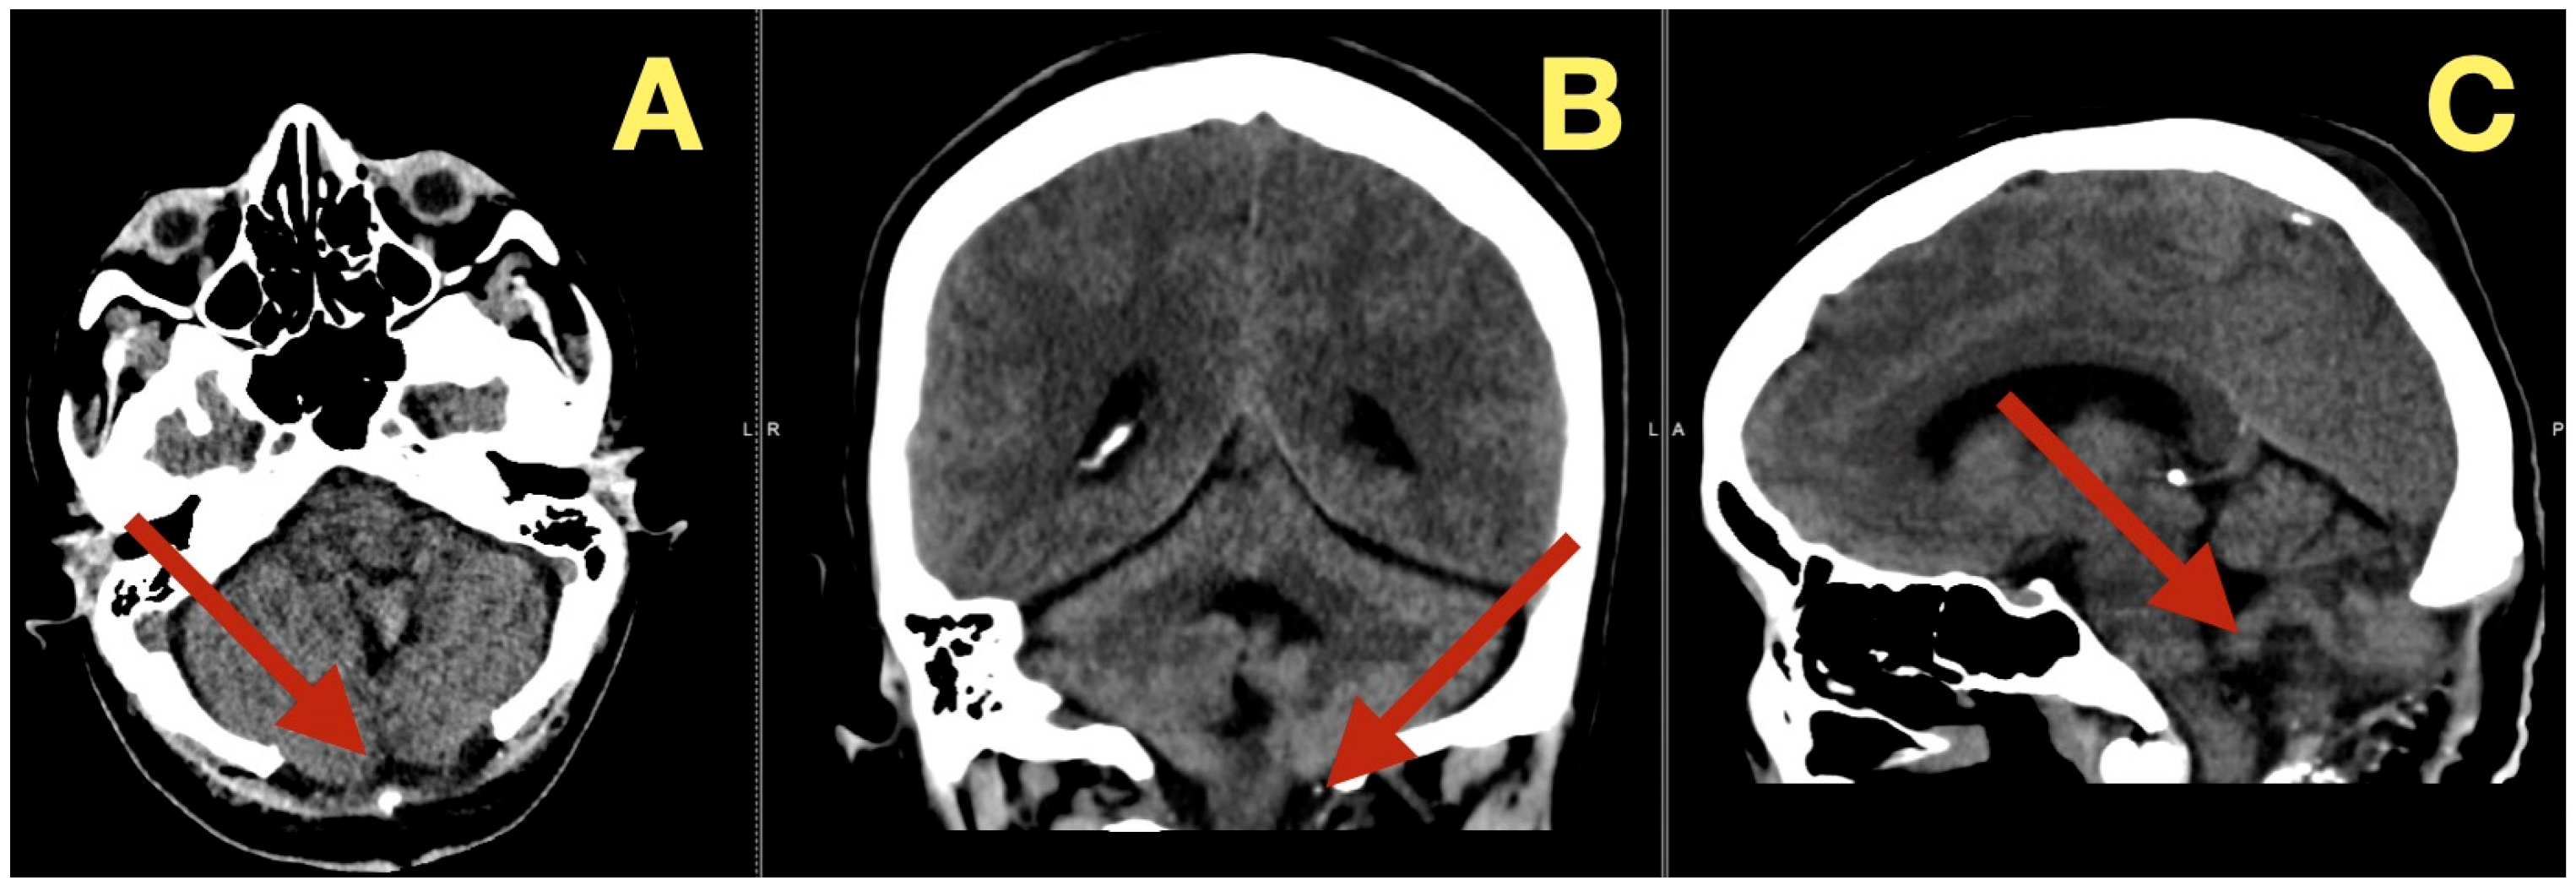

In addition to its rarity, the case also stood out due to the fact that all of the patient’s preoperative angiograms revealed a normal architecture of cerebral vasculature and no indication of aneurisms, arteriovenous malformations, or impaired venous outflow (Figure 2A,B). Further, the Circle of Willis was fully developed and symmetrically distributed, and the dural venous sinuses were unobstructed. As such, these studies ruled out vascular-related causes of intracranial hypertension and were consistent with a slowly expanding, avascular lesion.

Radiologically, the tumor was identified as a nonenhancing, avascular midline fourth-ventricular mass compressing the dorsal brainstem and resulting in secondary supratentorial ventriculomegaly. The intraoperative anatomy was correctly predicted: the lesion was avascular, white, waxy and was 39 × 37 × 55 mm in size.

Figure 2. Preoperative vascular imaging. (A): Frontal MRA maximum-intensity projection: normal configuration of the circle of Willis without aneurysm or stenosis (B): Lateral MRA: preserved arterial flow and patent dural venous sinuses, excluding vascular or venous causes of intracranial hypertension; the pressure increase is attributable to CSF-outflow obstruction by the fourth-ventricular mass.